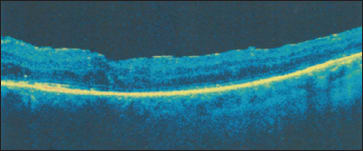

Figure 2. After treatment with MPLT, the same patient from Figure 1 showed dramatic improvement, with central retinal thickness decreasing from 438 μm to 270 μm.

Three months post-MPLT the patient had central retinal thickness of 270 μm and visual acuity of 20/60, a dramatic improvement (Figure 2).